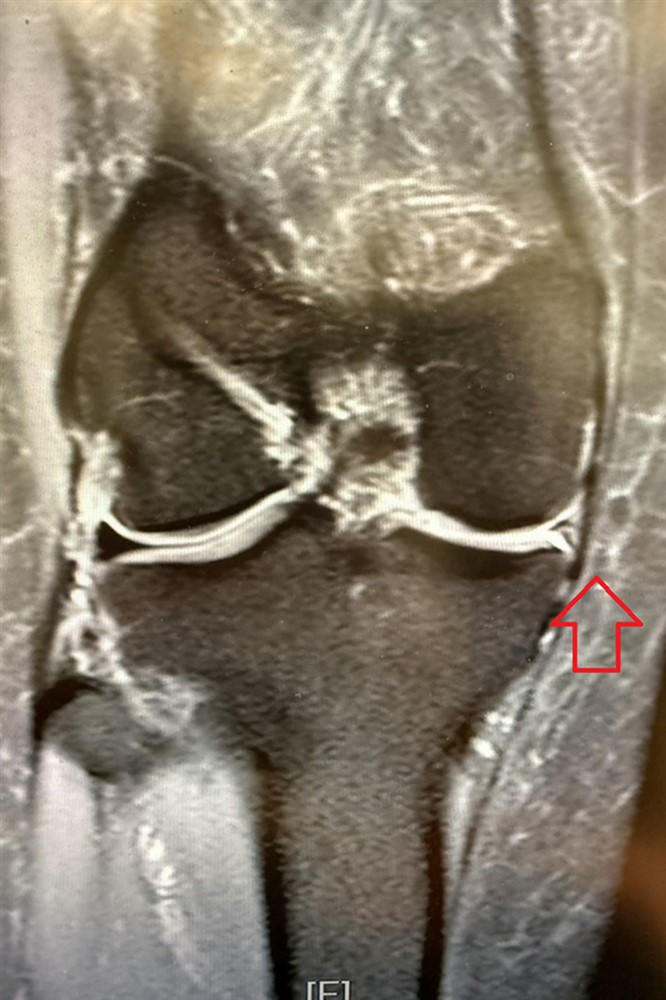

經過理學檢查、核磁造影檢查,發現是前十字韌帶斷裂,而內側半月軟骨卻不見蹤跡,懷疑是前一次手術的預後不佳導致碎裂。林坤輝醫師幫她進行「前十字韌帶重建及半月軟骨移植手術」,術後五天順利出院,並定期復健。

手術前,核磁造影檢查顯示半月軟骨消失(左);手術後半年,可見移植的半月軟骨(右)。圖/台北慈院提供